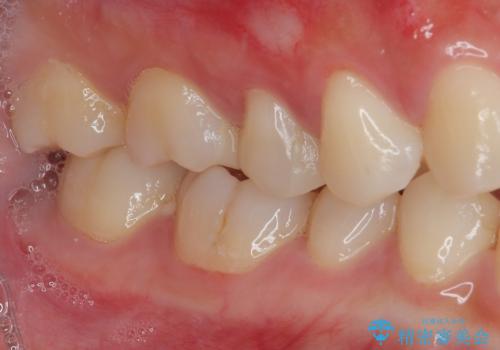

- 右上の銀歯を外したいとのことで来院された患者様です。検査後ハイブリッドインレーにて修復治療を行うことにしました。

見た目、機能面共に大変喜んでいただきました。

歯と歯の間の虫歯をコンポジットレジンや保険のメタルインレーで治すと段差ができたりして清掃性が悪くなるので、セラミックインレー修復やゴールドインレー修復などの適合の良い詰め物で治療することをオススメします。